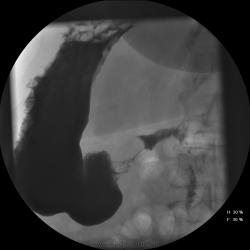

Женищина 49 лет, повышенного питания, обратилась с жалобами на потерю аппетита, жжение после чуть острой пищи, отрыжку с неприятным запахом, иногда темный стул, несколько похудела. Данные жалобы с сентебря-октября. Никуда не обращалась, коррегировала питанием. В последнее время стало хуже, обратилась...

Привратник удлиннен и ригиден, такое бывает при раке. Рек. ЭГДС.

Вы правы. я несколько недорасказал. женщина пришла уже с фгдс - инфильтративно-язвенный процесс в выходном отеде желудка у привратника по малой кривизне с переходом на переднюю стенку. так что прицельно смотрел этот отдел. перистальтка была ослаблена, краевой дефект в препилорической зоне по малой кривизне, передней стенке, кажущееся удлинение привратника, нависание основания луковицы - вообщем как в книжке. эвакуация было не изменена. написал рак выходного отдела желудка. вчера пришла гистология - высокодиф-я аденокарцинома. вот такая история.

Пока, касаясь только луковицы, но не препилорического отдела. "Ниши" в луковице есть, и они нуждаются в объяснении.

Конечно, в пилорическом канале уже растет, и "это" растет, уже и препилорической части и в луковице 12-ти перстной кишки.